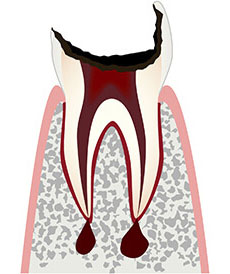

むし歯の大きさはC1〜4と表され、数値が大きくなるほど大きいむし歯を意味します。

歯髄(神経)まで及んだむし歯→根管治療後被せ物治療

歯のほとんどがむし歯→抜歯治療